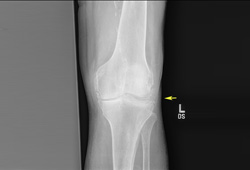

Depósito de pirofosfato de cálcio

Radiografia de joelho com depósitos calcificados lineares de calcificação de cartilagem

Da coleção pessoal de Ann K. Rosenthal, MD